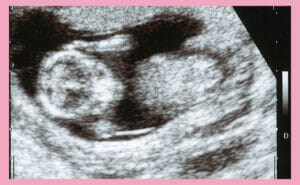

Down Syndrome visible in an Ultr…

• 2025.10.15

• Down syndrome, all autosomal whole region partial deletions and duplications

• Down Syndrome (Trisomy 21)

• During Pregnancy

• NIPT (New Non-invasive Prenatal Testing)

• Pregnancy

• Pregnancy Checkup

• Pregnancy Health Examination